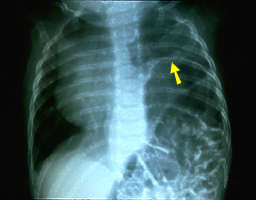

Rayos X del pecho que muestran un desplazamiento del diafragma como resultado de una lesión del nervio frénico.

Estos rayos X muestran un desplazamiento marcado hacia arriba del diafragma lejos del nivel normal; se ven tripas en la cavidad del pecho. Parálisis del diafragma puede resolverse espontáneamente pero requiere atención particular porque puede causar la muerte. Pliegue del diafragma por un cirujano del pecho e injerción de nervios al nervio frénico son tratamientos alternativos para una lesión del nervio frénico.